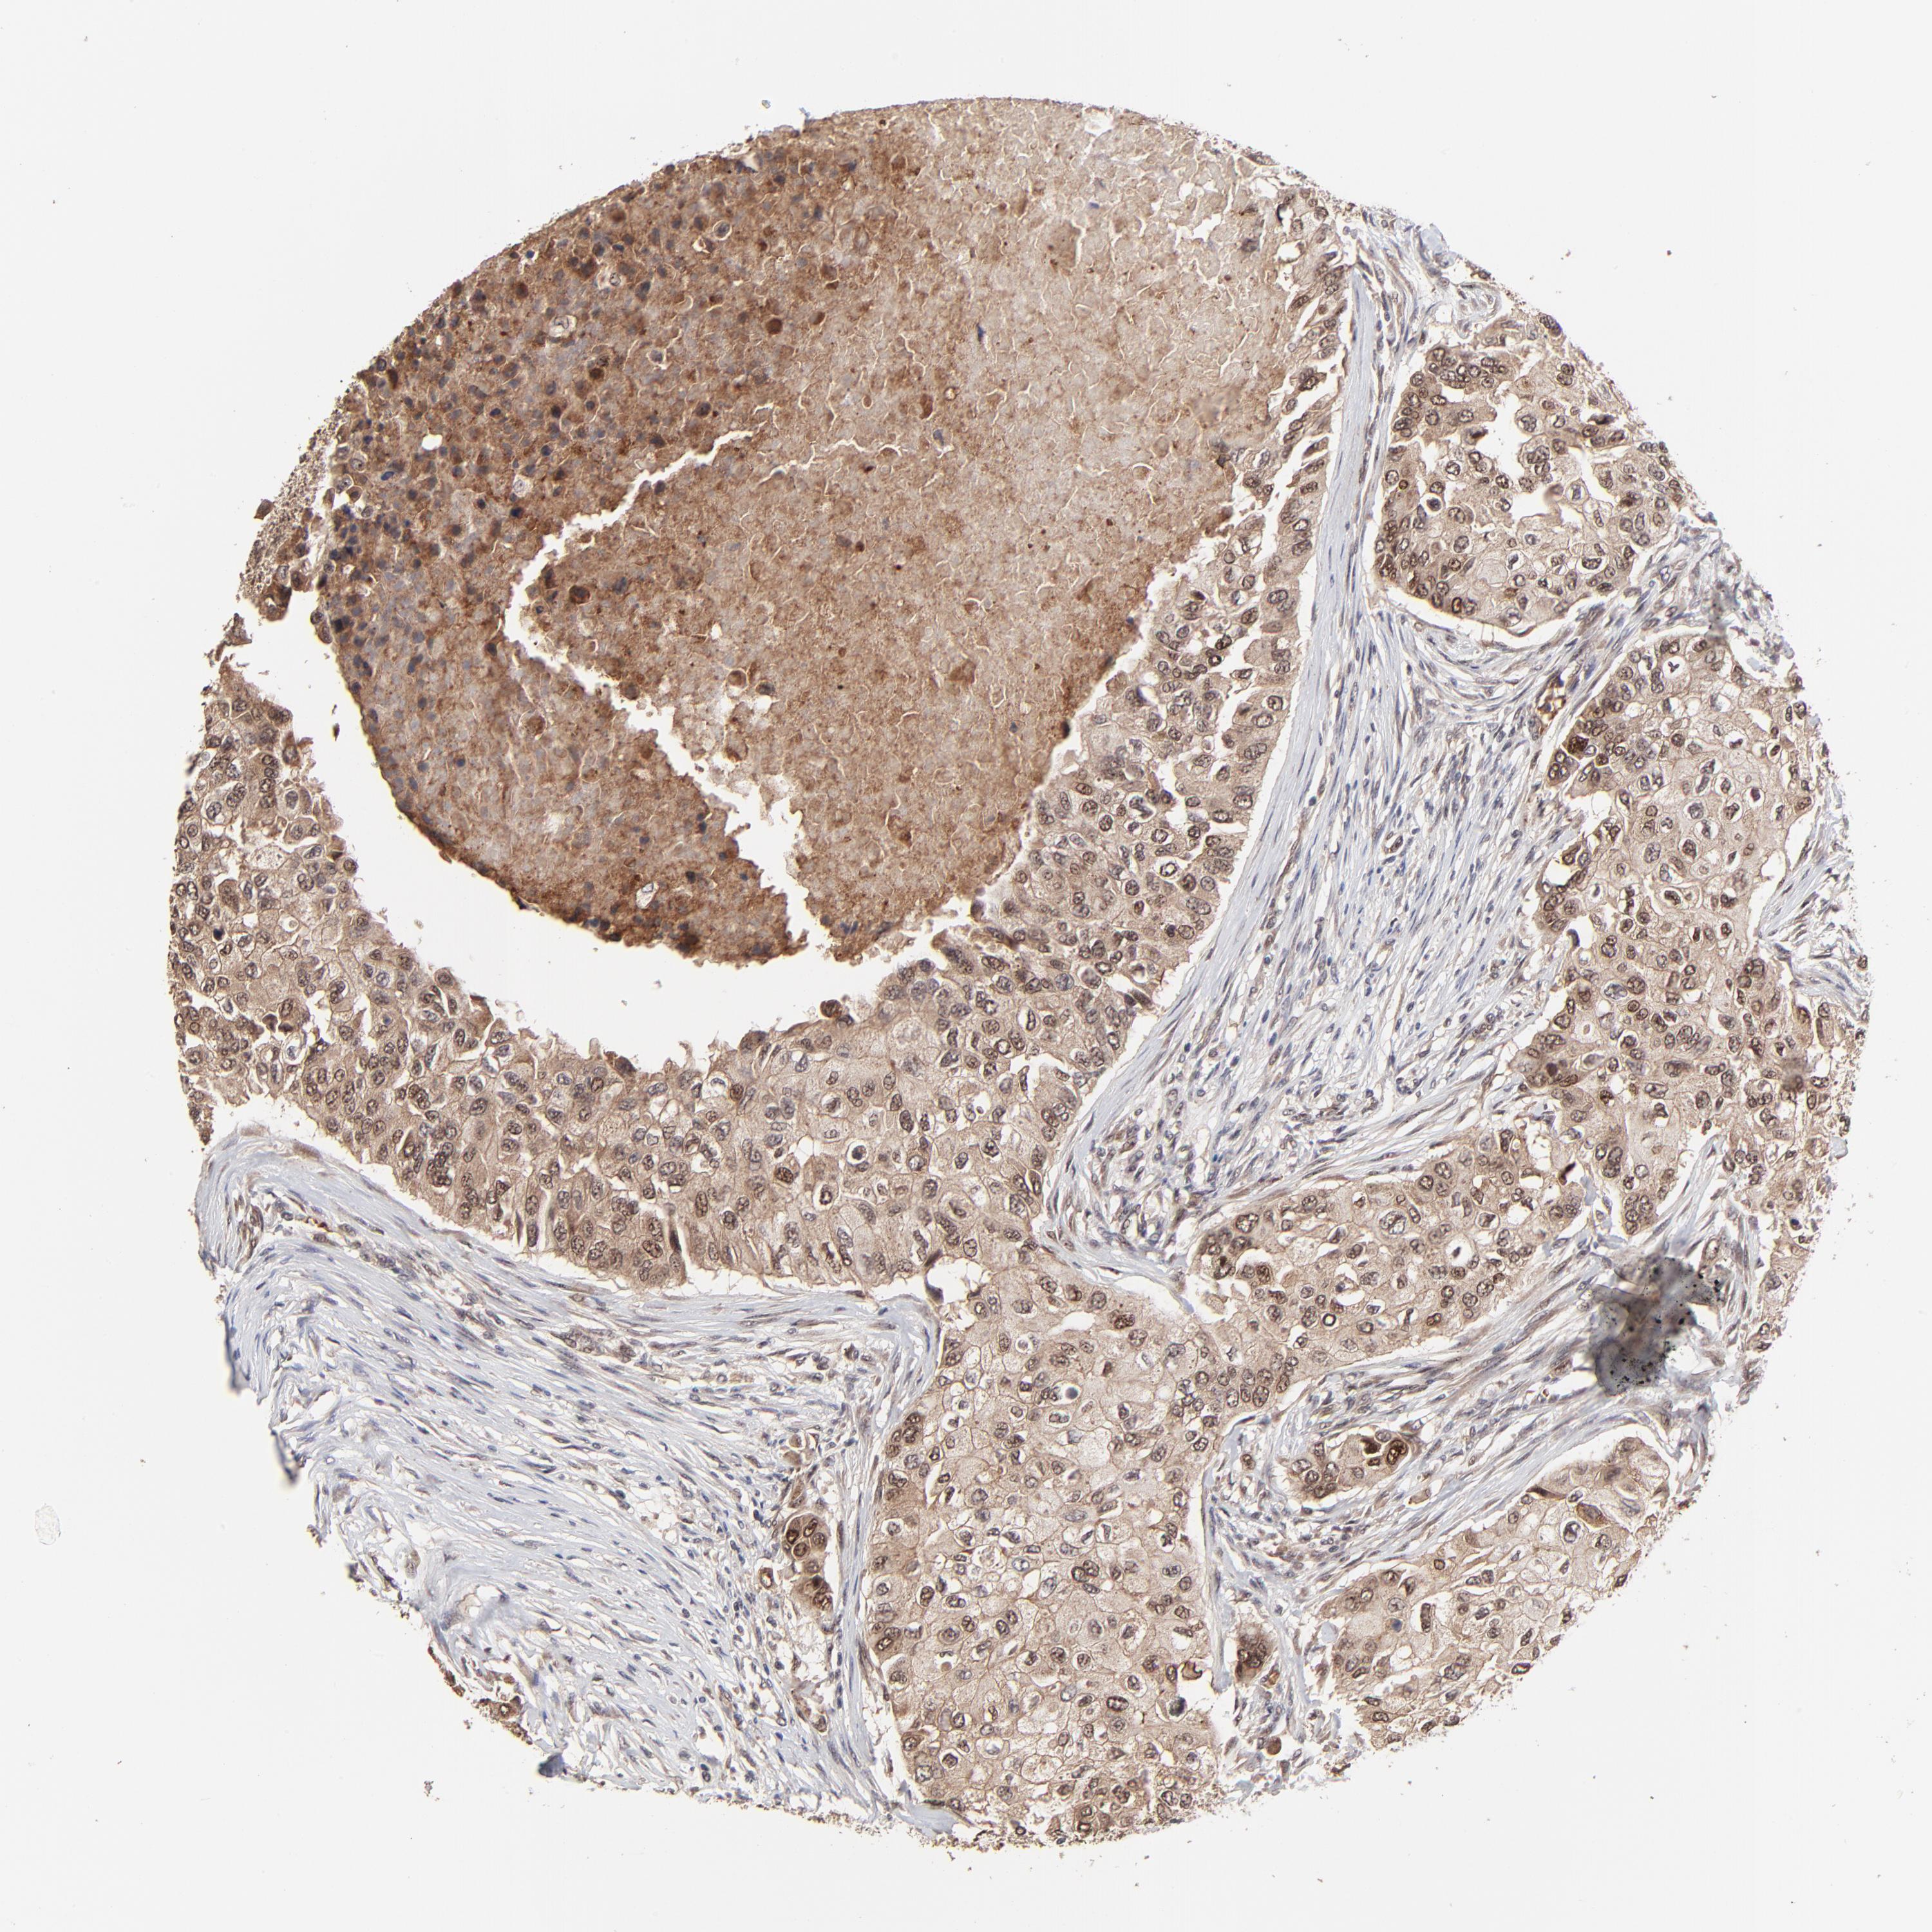

BRCA TCGA BRCA VALIDATION PROTEIN EXPRESSION